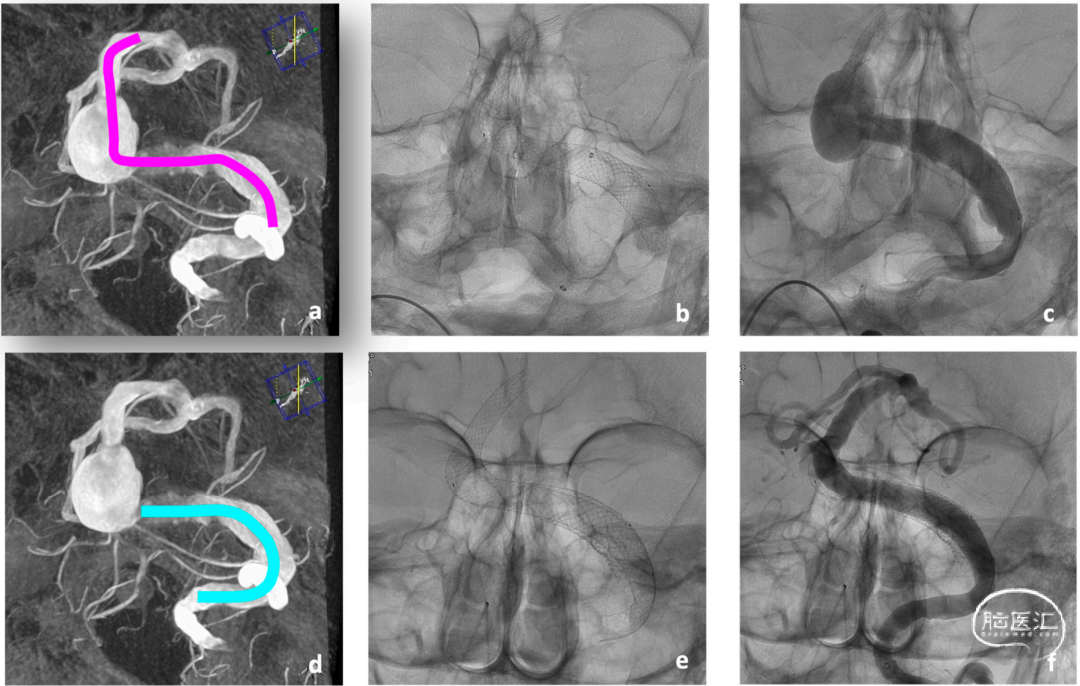

图3. 患者1使用3枚Accero®-Rex支架和一个血流导向装置对基底动脉瘤和左侧椎动脉V4段扩张进行分期治疗影像资料。a、d. 为手术计划概要图,粉色为Accero®-Rex支架,蓝绿色为血流导向装置;b. 一期植入3枚Accero®-Rex支架;c. 植入血管支架后即刻造影见动脉瘤形态未发生明显变化;f. 血流导向装置植入后1周基底动脉和左侧椎动脉V4段发生了明显的血管重塑;e. 沿血栓形成部分的近端植入血流导向装置。

一期治疗时,将Neuron Max® 6F 80cm长鞘送至左侧椎动脉,然后同轴地将一条Sofia EX中间导管送至椎动脉V3段。搭配0.0014”导丝很容易通过动脉瘤。由于这种大型支架输送导管的相对刚性,NeuroSlider 39®只能达到基底动脉近端。相反,中间导管可以通过使用Rebar-18微导管和不同微导丝的四轴途径进入至左侧大脑后动脉P1段。在这个稳定的位置,NeuroSlider 39®可以被带到中间导管的顶端,便于部署第一个最远端的支架,总共植入三枚支架(1枚10x60mm、2枚10x30mm Accero®-Rex支架)被释放以覆盖动脉瘤颈。术中无技术相关并发症发生。